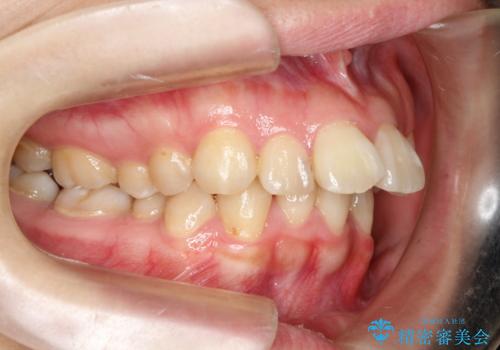

飛び出した前歯を引っ込めたい 目立たないワイヤーでの抜歯矯正

- 口元の閉じにくさと、前歯のでこぼこの歯並びを気にして来院された患者様です。

口元を積極的に引っ込めるために、上下左右の小臼歯計4本を抜歯することとしました。

咬み合わせが深く、咬合力強いため、補助装置を使用しながら積極的に口元を下げることとしました。